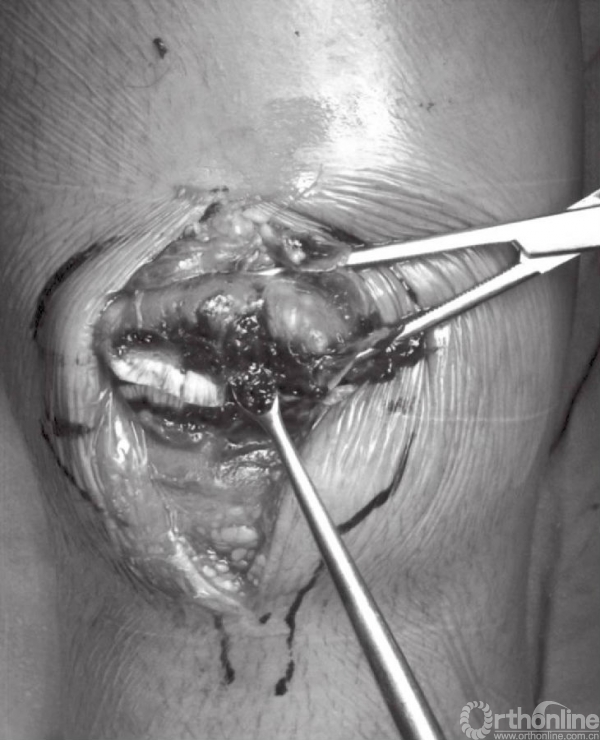

骨折末端应以小挂勺以及吸引器清除局部的血凝块。骨折端处的骨膜以及韧带应分离至骨折线周围2~3cm处,以免影响骨折复位。但应注意,不要清除髌骨周围过多的软组织,因为常有骨折块包含其中。

应仔细探查关节,以辨识游离骨块以及关节面损伤(图6)。此时,可对骨折进行复位,并以复位钳进行临时固定。检查骨折复位情况以及关节稳定性,关节内骨块的解剖复位是非常重要的。术中复位困难,可能是因为小骨块或者软组织嵌于骨折端。

图6 应仔细探查关节以辨识游离骨块以及关节面损伤